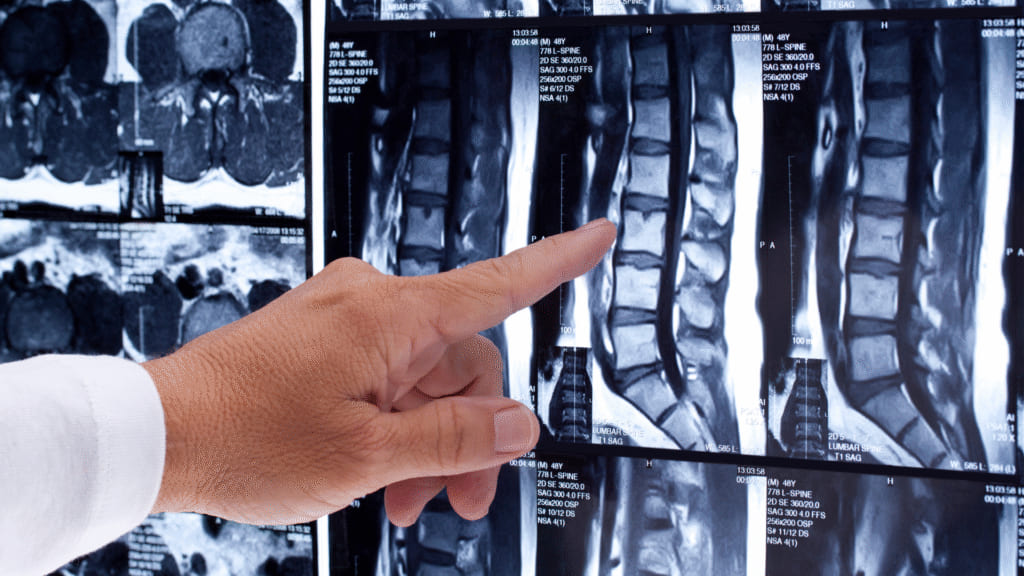

This is one of the strongest beliefs people carry. But large imaging studies show a very different story.

• Up to 80 to 90 percent of people with no back pain at all have disc bulges, disc degeneration, or joint wear and tear visible on MRI.

• At the same time, many people with significant back pain show no serious structural damage on scans.

These so-called abnormalities are often normal, age-related changes, not the direct cause of pain.

Pain is not a direct measure of tissue damage. Pain reflects how sensitive and protective the nervous system has become.

PHOTO #1